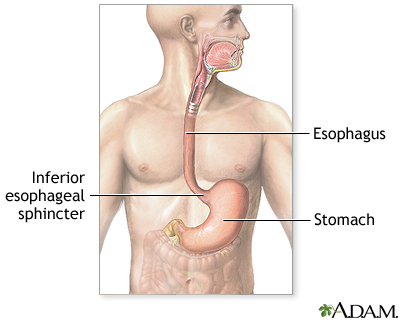

A lower esophageal ring is an abnormal ring of tissue that forms where the esophagus (the tube from the mouth to the stomach) and stomach meet.

A lower esophageal ring is a narrowing of the esophagus that occurs in a small number of people. The cause of the problem is unclear, but many believe that it is caused by acid reflux.